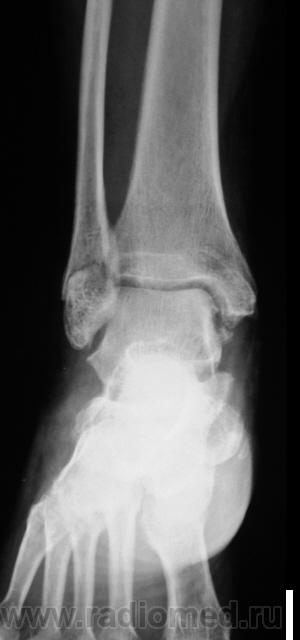

Травма. Пациент направлен на рентгенографию голеностопного сустава.